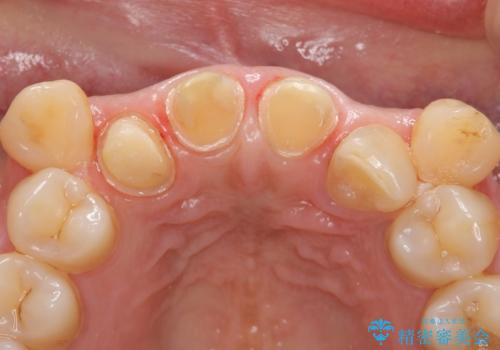

右上2は歯の神経が死んでおり、根尖病変を認めたため根管治療を行いました。

その後右上1,2番目及び左上1番目の歯に対してオールセラミッククラウンによる補綴を行いました。